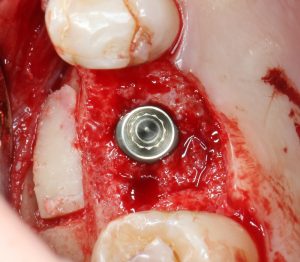

Приступаем к установке имплантата.

Кстати, комплект поставки не содержит ни заглушки, ни абатмента. А сам имплантат фиксируется на ключе простым заклиниванием платформы. Т. е. не слишком надёжно:

По этому поводу существует поговорка: «Кто не ронял имплантаты Astra Tech, тот не работал с имплантатами Astra Tech«. В общем, будьте аккуратны, в идеале, проводите все манипуляции по фиксации имплантата на ключе над столом.

Если лунка подготовлена правильно, то имплантат проваливается в неё почти полностью:

и докручивается до правильного положения несколькими оборотами.

Еще раз акцентирую внимание на том, что Astra Tech — субгингивальная имплантационная система. А это значит, что для неё выполняются те же правила позиционирования, что и для других субгингивальных имплантационных систем. Читайте здесь>>.

Теперь заглушка. Упаковка заглушки еще более неудобная, чем упаковка имплантата:

Напомню, что все компоненты имплантационной системы Astra Tech одноразовые. Следовательно, многоразовое (в целях экономии) использование заглушек и формирователей десны неприемлемо: